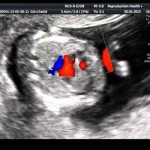

The first step necessary to select adequate treatment is an accurate diagnosis of ES with determination of its origin (ventricular or supraventricular). It is not difficult to suspect that a patient has ES when it is subjectively felt. Often the most unpleasant for the patient is “harmless” functional SE. With ventricular extrasystole (VES), the symptoms are more pronounced, apparently due to an increase in the duration of the pause (a feeling of “cardiac arrest” and a stronger first post-extrasystolic contraction of the heart). To make a diagnosis of ES, a standard ECG in combination with Holter monitoring (HM) is sufficient. Diagnosis of supraventricular extrasystole (SVES) can be difficult in the presence of a wide (E 0.12 s, due to aberrant conduction) QRS complex on the ECG, in most cases - as a right bundle branch block; “early” NVES (superposition of the P wave on the preceding T may cause an error in identifying the P wave); blocked NVES (premature P wave not conducted to the ventricles). To differentiate between VES and NVES with aberrant conduction, a comparison of the shape and coupling interval with previously recorded extrasystoles should be used.

CM is carried out to verify the diagnosis of PVCs (especially in the presence of rare extrasystoles that cannot be recorded on a standard ECG), to determine the mono- and polymorphism of PVCs and mainly to determine the number of PVCs during the day, their distribution by time of day and their relationship with various factors. . The presence of no more than 30 ES per hour is considered acceptable. Shorter monitoring may be used (for example, to assess the effectiveness of treatment). ES can also be first detected during various stress ECG tests. If there is a clear anamnestic connection between the occurrence of ES and exercise, these tests can be performed specifically to verify the diagnosis of ES (usually ventricular); in these cases, conditions must be created for possible resuscitation. The association of PVCs with exercise most likely indicates their ischemic etiology.